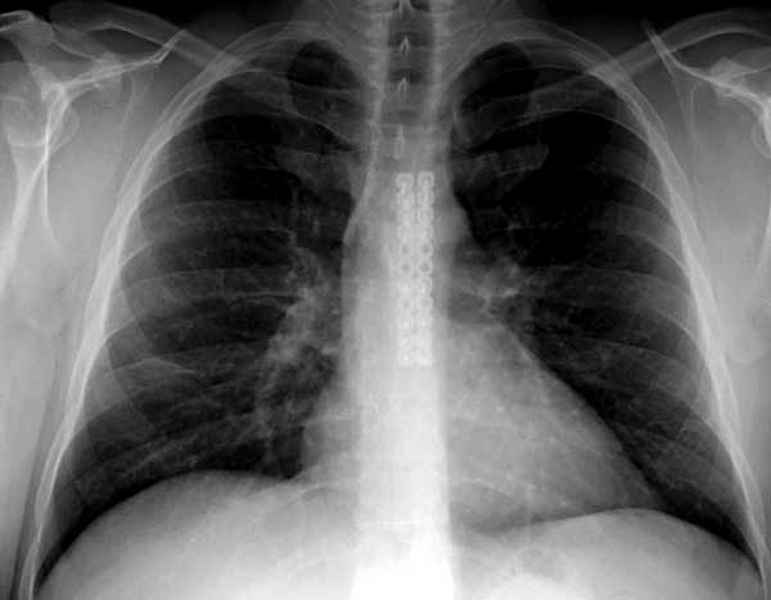

Юра, интересно, насколько такой остеосинтез контролирует степень репозиции, а то у меня имеются снимки девочки 11 лет, направленной ко мне на консультацию из одной из республик бывшего союза.

После торакальной операции, по-видимому, сильно натянули проволоку, и в результате получился захлест отломков в друг друга.

Оперировавший хирург предлагает подождать, а родителей беспокоит проблема прогрессирующей ассиметрии лица, как при кривошее.

А простые посттравматические ложные суставы грудины приходилось оперировать с ограничителем сверла и с фиксацией 2.4 мм пластинами с угловой стабильностью.